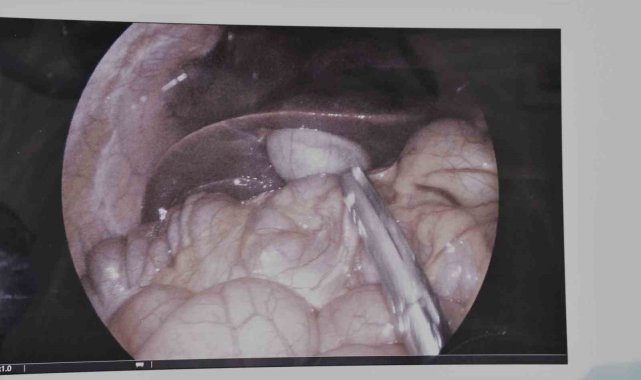

Yozgat Şehir Hastanesi'nde, çocuk cerrahisi alanında önemli bir ameliyat gerçekleştirildiSık sık tekrarlayan safra kesesi iltihaplanması (kolesistit) şikayeti bulunan 17 yaşındaki bir hasta, hastanede çocuk yaş grubunda ilk kez gerçekleştirilen laparoskopik kolesistektomi ameliyatı ile sağlığına kavuştu.Operasyonu gerçekleştiren Çocuk Cerrahisi Uzmanı Op. Dr. Serkan Odabaşı, yaptığı açıklamada, hastanın uzun süredir karın ağrısı, mide bulantısı ve sindirim problemleri şikayetleri olduğunu belirtti. Dr. Odabaşı, yapılan detaylı tetkikler sonucunda safra kesesinde enfeksiyon tespit edildiğini ifade ederken, "Bu durumda en uygun tedavi yöntemi, safra kesesinin alınması yani kolesistektomi ameliyatıdır. Operasyonu kapalı (laparoskopik) yöntemle gerçekleştirdik. Laparoskopik cerrahi, karında büyük kesiler açmadan, küçük delikler aracılığıyla özel cerrahi aletlerle yapılan modern bir tekniktir. Bu sayede hastamızın ameliyatı başarılı bir şekilde tamamlandı. Hastamızın kısa sürede taburcu edilmesi planlanmaktadır" dedi.Yozgat Şehir Hastanesi Başhekimi Uz. Dr. Mustafa Kozan da operasyonun önemine değinerek, safra kesesi taşlarının çocuklarda nadir görüldüğünü ancak ciddi sağlık sorunlarına yol açabileceğini vurguladı.Başhekim Kozan, "Safra kesesi taşları, safra kesesinde biriken kristalleşmiş maddelerden oluşur. Çocuk yaş grubunda nadir görülmesine rağmen ciddi karın ağrısı, mide bulantısı, kusma ve sindirim sorunlarına neden olabilir. Obezite, hemolitik hastalıklar, hızlı kilo kaybı, genetik yatkınlık ve bazı beslenme alışkanlıkları çocuklarda safra taşı oluşumuna neden olabilir. Hafif vakalarda diyet düzenlemesi ve ilaç tedavisi yeterli olabilir. Ancak, sık tekrarlayan ağrılar, safra yollarında tıkanma veya iltihaplanma durumlarında cerrahi müdahale gerekebilir" şeklinde bilgi verdi.Pediatrik laparoskopik cerrahinin çocuk hastalar için büyük bir avantaj sağladığını belirten Kozan, bu tür operasyonların yaygınlaştırılması ve daha fazla çocuğun modern cerrahi tekniklerden faydalanması için çalışmaların sürdüğünü ifade etti.